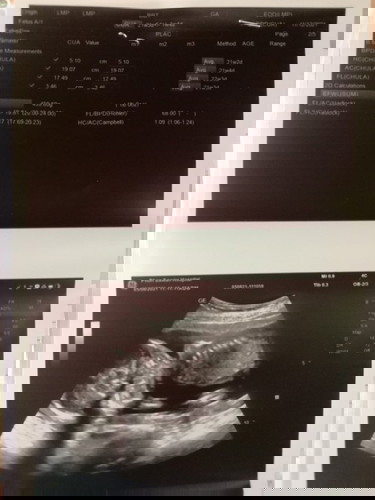

แม่ๆช่วยดูให้หน่อยค่ะ พอดีไปอัลตร้าซาวด์เมื่อวานมา คุนหมอบอกแค่น้องแข็งแรงดี แต่คุนหมอก็ไม่ได้บอกน้ำหนักของน้อง เพศก็ไม่ได้บอก 5เดือนแล้วค่ะยังไม่รุ้เลย แม่ๆช่วยดูจากภาพอัลตร้าซาวด์ให้หน่อยค่ะ ว่าน้ำหนักน้องตามเกณฑ์มั้ย ช. หรือ ญ ค่ะ#ขอคำแนะนำหน่อยค่ะ #ขอบคุณล่วงหน้านะคะ #ขอบคุณสำหรับคำตอบค่ะ #ท้องแรกคะ